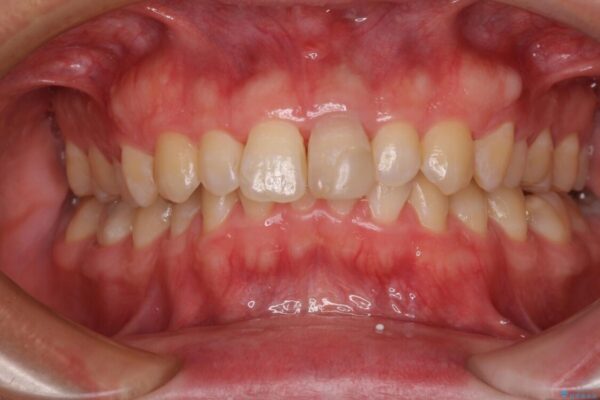

神経を取り除いた歯は時間とともに変色してきます。

クリーニングやホワイトニングでは改善できないため、オールセラミッククラウンなどによる補綴治療が必要となります。

治療後

• 変色した前歯をオールセラミッククラウンに 治療後画像